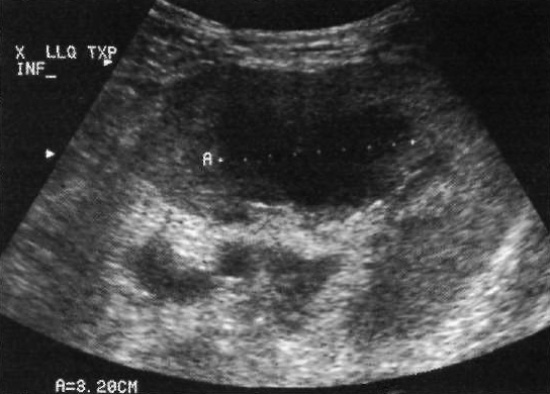

Посттрансплантационное лимфопролиферативное заболевание (ПТЛЗ) – прелимфомное состояние, возникающее менее чем у 23% больных после трансплантации почки, которое может спонтанно разрешаться после прекращения иммуносупрессивной терапии. ПТЛЗ обусловлено вирусом Эпштейн-Барр. Нужно отметить, что может поражаться любой орган, не только трансплантат. Патология может быть отсроченной – возникать через 6-24 месяца после пересадки органа. Отметим, что в последнее время частота развития ПТЛЗ значительно увеличилась, что обусловлено применением новых, более сильных иммуносупрессивных средств.

Ультразвуковая картина ПТЛЗ демонстрирует плотный, часто гипоэхогенный и васкуляризированный очаг. Гомогенный участок поражения может давать акустический эффект усиления (фото 14).

Фото 14. Посттрансплантационное лимфопролиферативное заболевание. На поперечном ультразвуковом изображении нижнего полюса трансплантата почки наблюдается гипоэхогенное образование, длиной 3,2 см. У пациента отсутствовали характерные симптомы. Образование разрешилось самостоятельно через 2 месяца после отмены иммуносупрессивной терапии